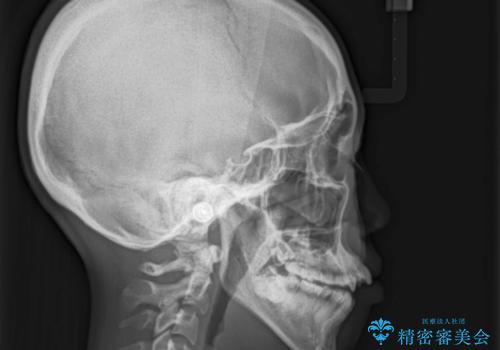

- 上顎の骨格性拡大+両側第1小臼歯抜歯 によりスペースを獲得、フルリンガルによるワイヤー矯正を計画した。

骨格的要因を背景にもつ不正咬合のため、歯列矯正単独での改善は困難と判断しましたが、患者さんとの相談の結果、歯列矯正単独で可能なところまで一緒に頑張りましょうということで、治療をすすめました。